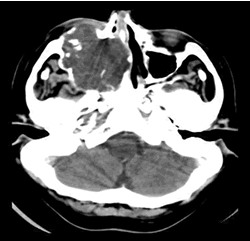

La TAC permite visualizar el contenido iso o hipodenso homogéneo con relación al parénquima cerebral que no capta contraste, solo el piocele se tiñe periféricamente (Fig. 5). Permite estudiar las diferentes reacciones de las paredes óseas: lisas, netas, delgadas de forma redondeada u oval (Fig. 6). Otros casos son irregulares y poco visibles. Puede formarse una banda gruesa y densa de osteocondensación por la reacción osteoblástica. Imágenes de invasión y osteólísis que plantean el diagnóstico diferencial con neoplasias las cuáles muestran una imagen heterogénea que realza con el contraste administrado. (4)

Un patrón es hiperintenso en T1 debido a un alto contenido proteico, e hiperintenso en T2 por su alto contenido acuoso. Estos mucoceles en Tomografía se ven moderadamente densos. (Fig. 7, 8 y 9)

Sea cual sea la vía de acceso, se amplía la apertura del seno para permitir el correcto drenaje y aireación del mismo y se extirpan las lesiones con sumo cuidado y sin brusquedad para favorecer la amplia marsupialización hacia la fosa nasal. (11) TAC. Postoperatoria que evidencia la marsupialización. (Fig. 11)